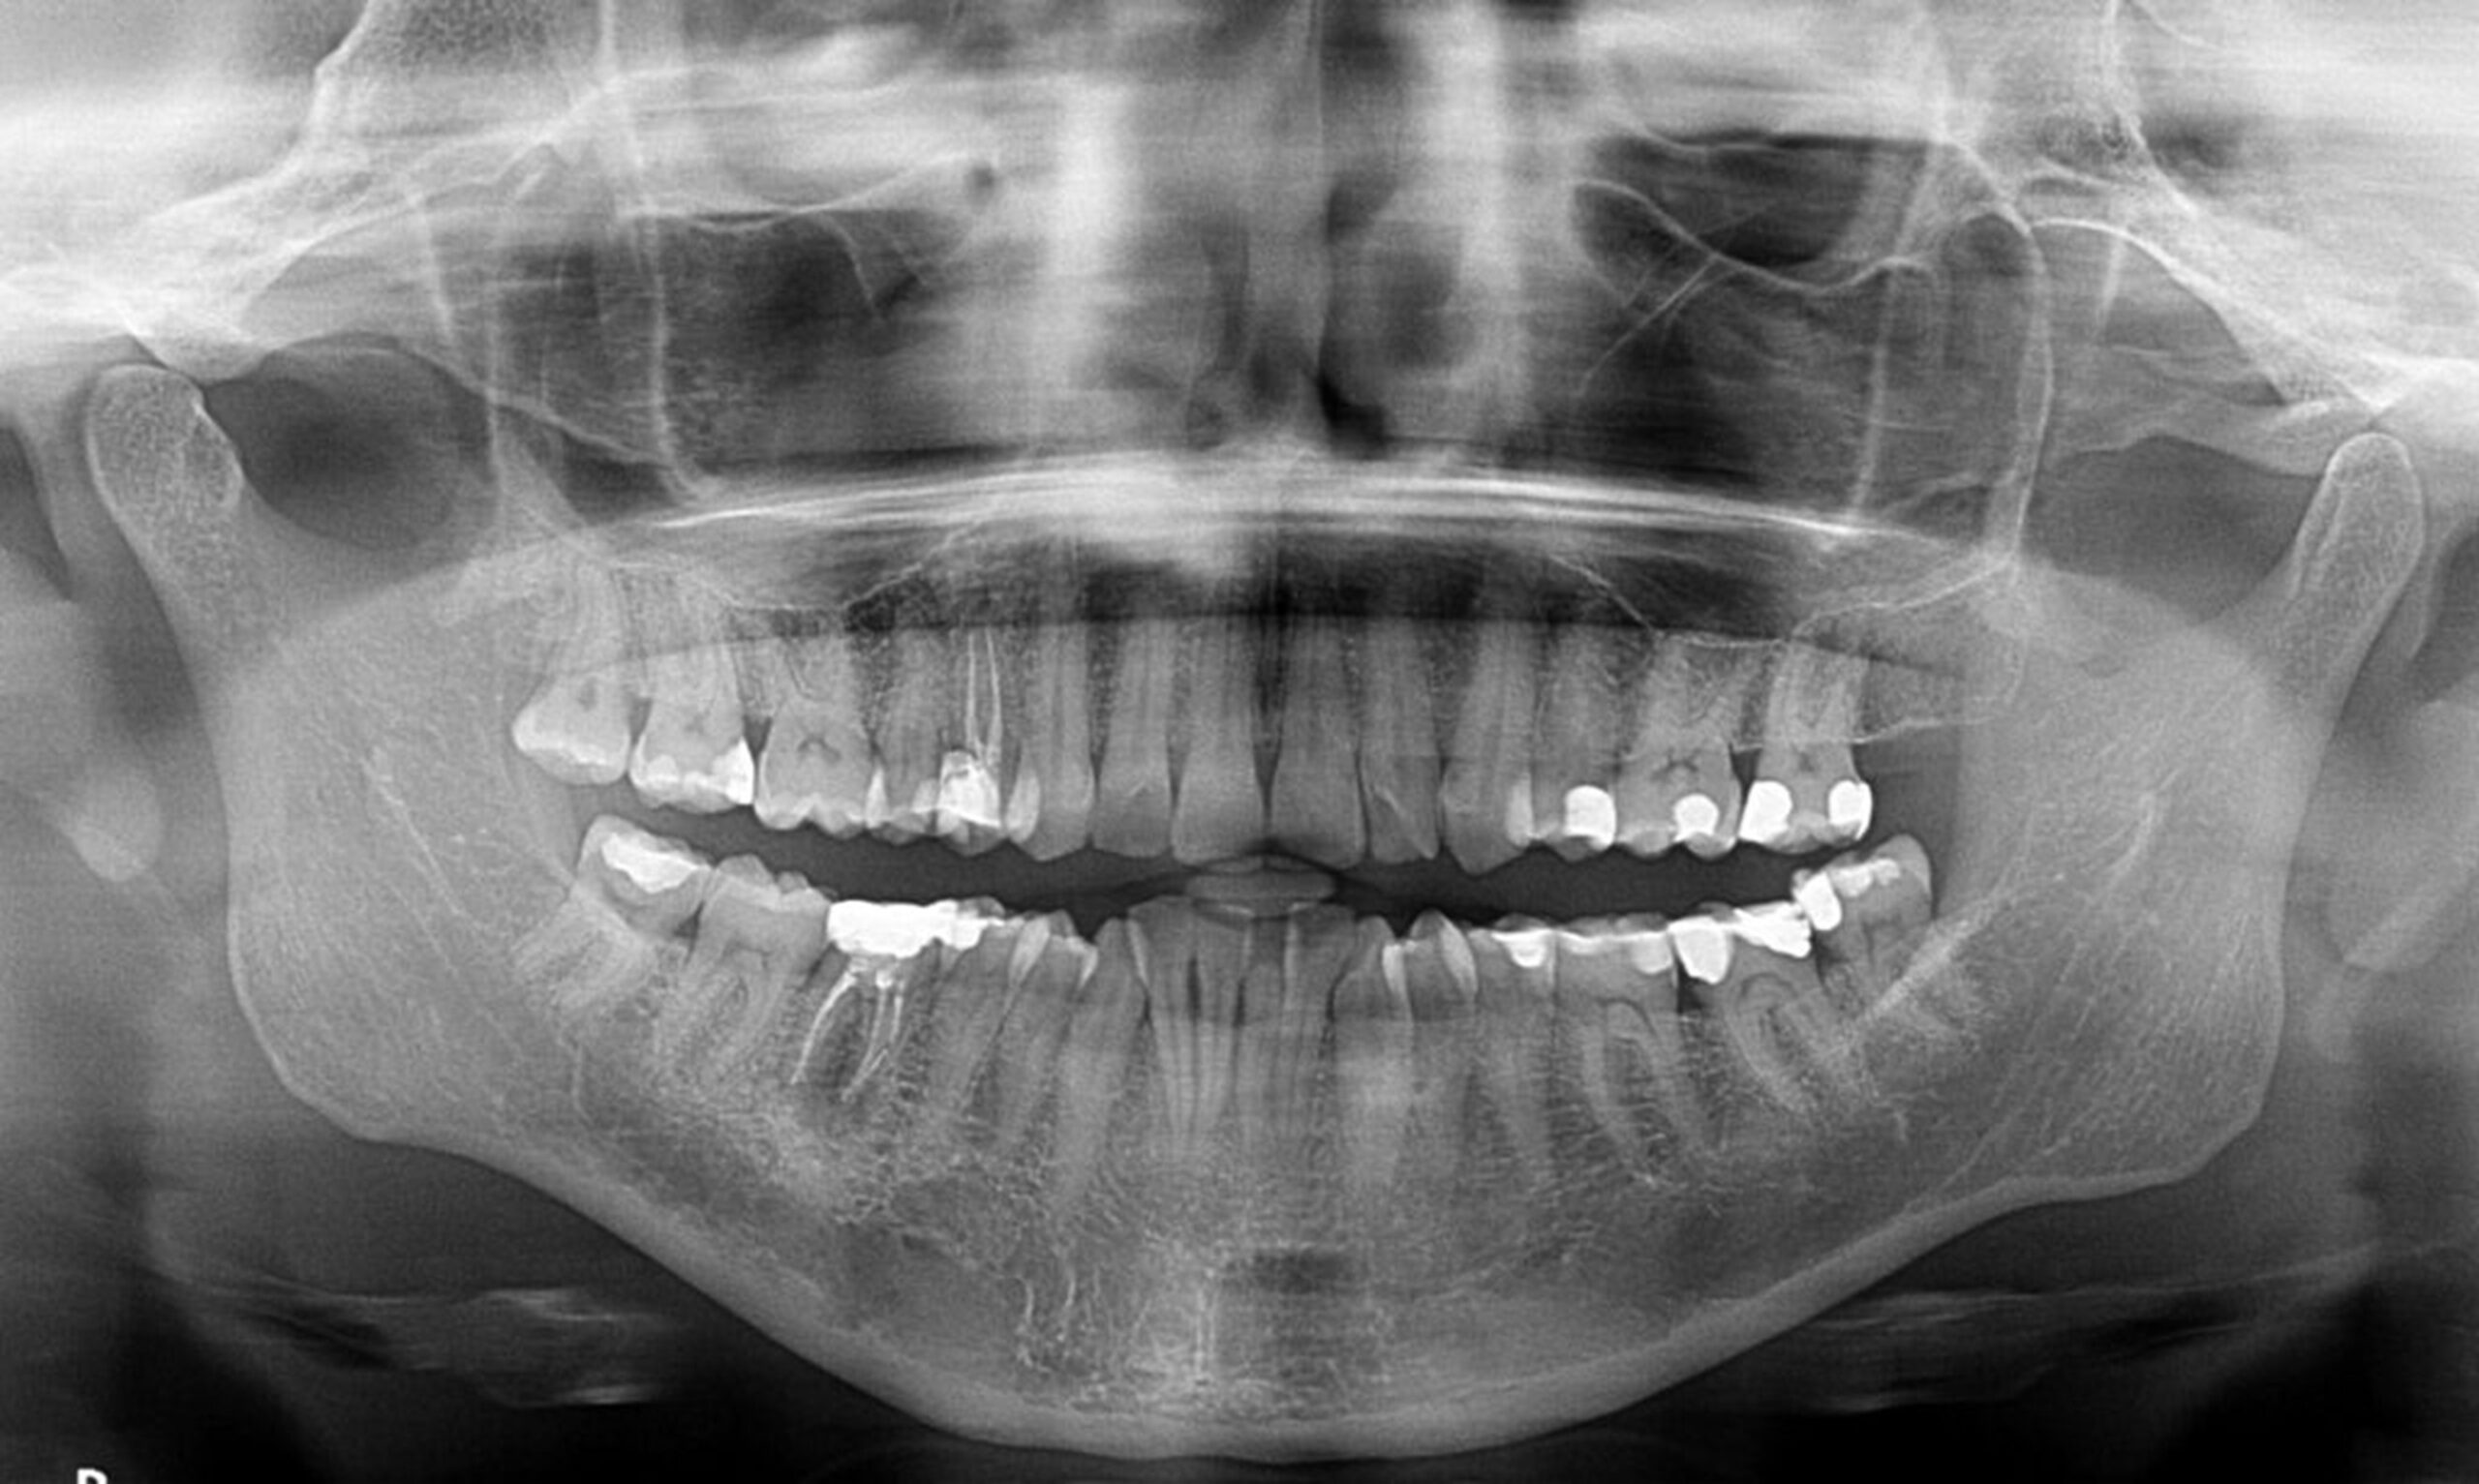

In deze cursus komt zeer uitgebreid de theorie aan bod over Röntgen. Onder andere het ontstaan, hoe röntgen werkt, welke regelgeving er is. Daarna komt de praktijk aan bod. Het maken van solo’s en bitewings wordt geleerd, maar ook het maken van de OPT en RSP, en we leren te beoordelen wat een goede foto is.

De oorsprong en theorie van röntgen, de toepassingsmogelijkheden, de negatieve invloed van röntgenstraling op het menselijk lichaam en contra-indicaties voor het maken van röntgenfoto’s, instelapparatuur en het gebruik hiervan, het maken van correcte solo’s en bitewings, en mogelijke fouten hierbij, het maken van correcte OPT’s en RSP’s en mogelijke fouten hierbij.